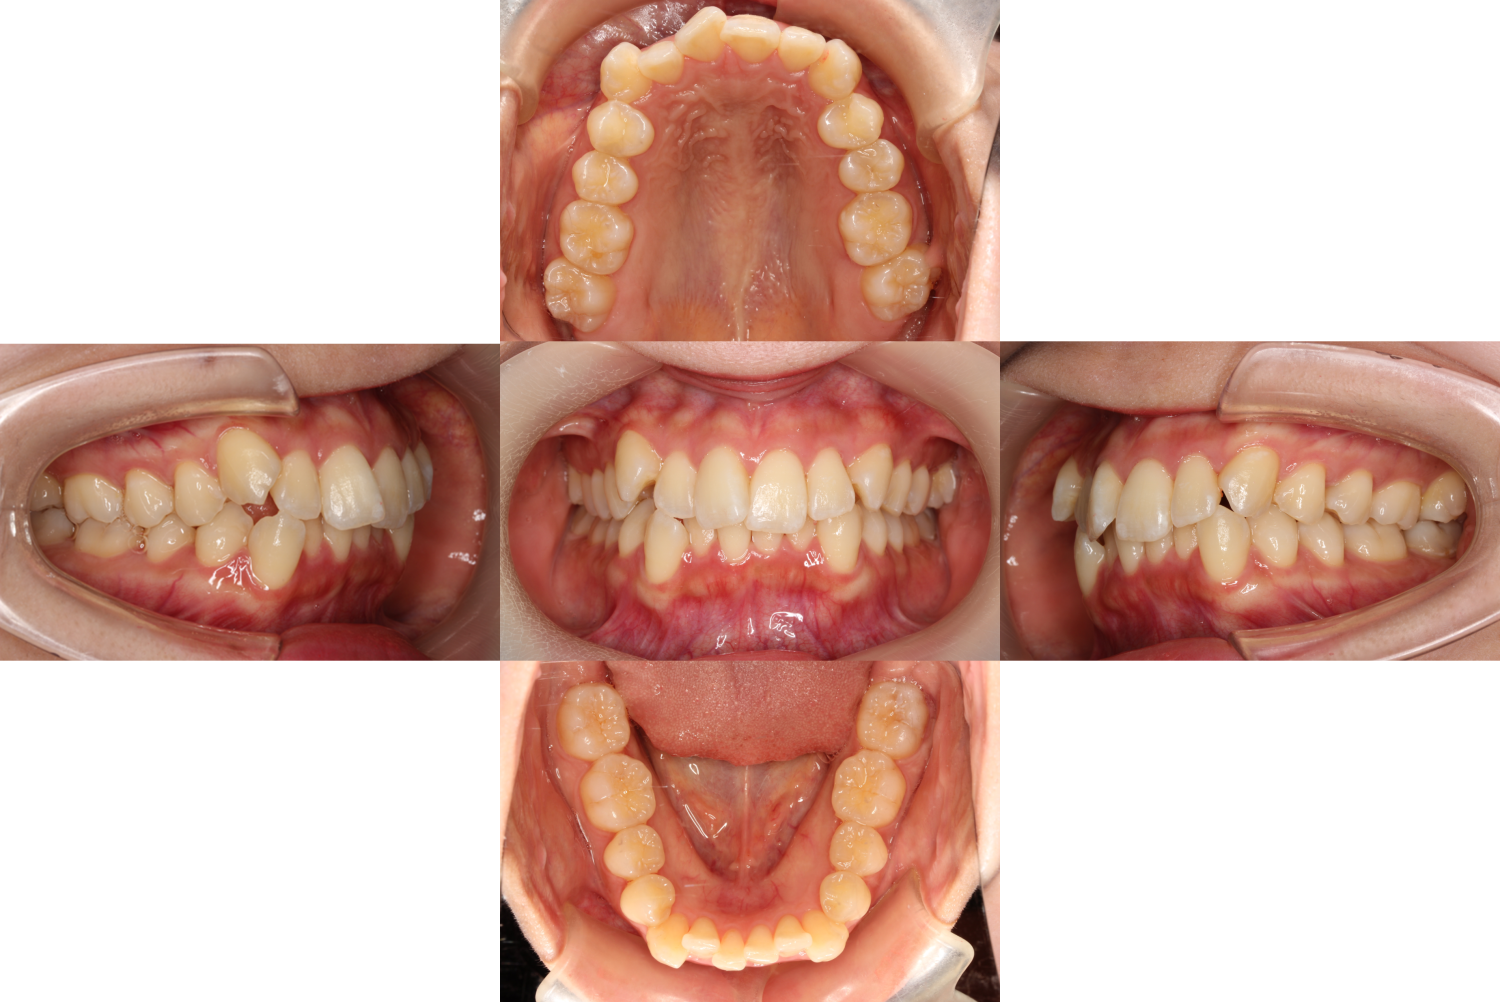

初診時の口腔内です。

【八重歯と上下前歯の凸凹】を気にしてカウンセリングにいらっしゃいました。